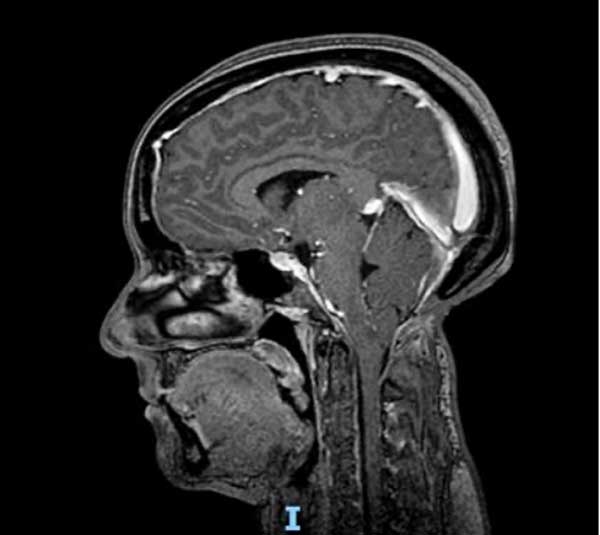

En el momento de la consulta, el examen físico presentó una leve paresia distal en ambos miembros superiores, hipoestesia termoalgésica en la mano y región subescapular izquierdas e hiperreflexia en ambos miembros inferiores. La resonancia magnética (RM) de encéfalo y columna cervical mostró un descenso marcado de las amígdalas cerebelosas con siringomielia cervicodorsal (Figura 1). Luego de la administración de contraste, se observó un refuerzo difuso de las meninges y senos venosos compatibles con hipotensión intracraneana (Figura 2). Ante la sospecha de una fístula espinal espontánea de LCR, se decidió realizar un estudio contrastado intratecal para determinar el sitio de la pérdida.

Figura 2. RM ponderada en T1 luego de la administración de contraste que muestra el refuerzo meníngeo.